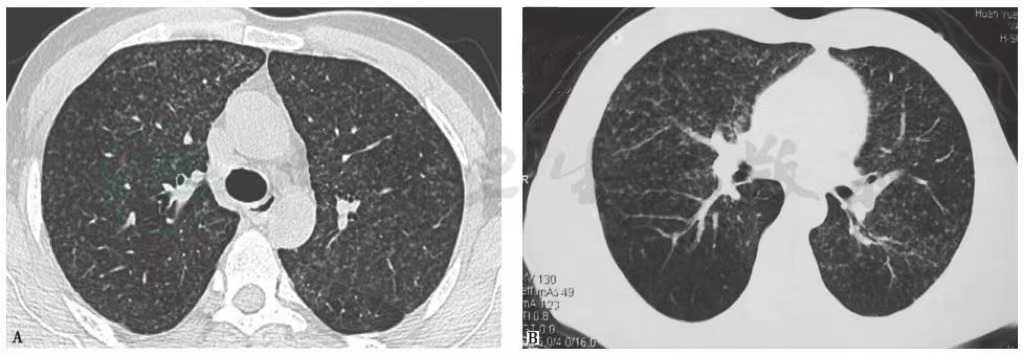

10天前胸部CT见双肺呈随机分布的弥漫性粟粒样小结节影(图2)。

图2 10天前胸部CT表现